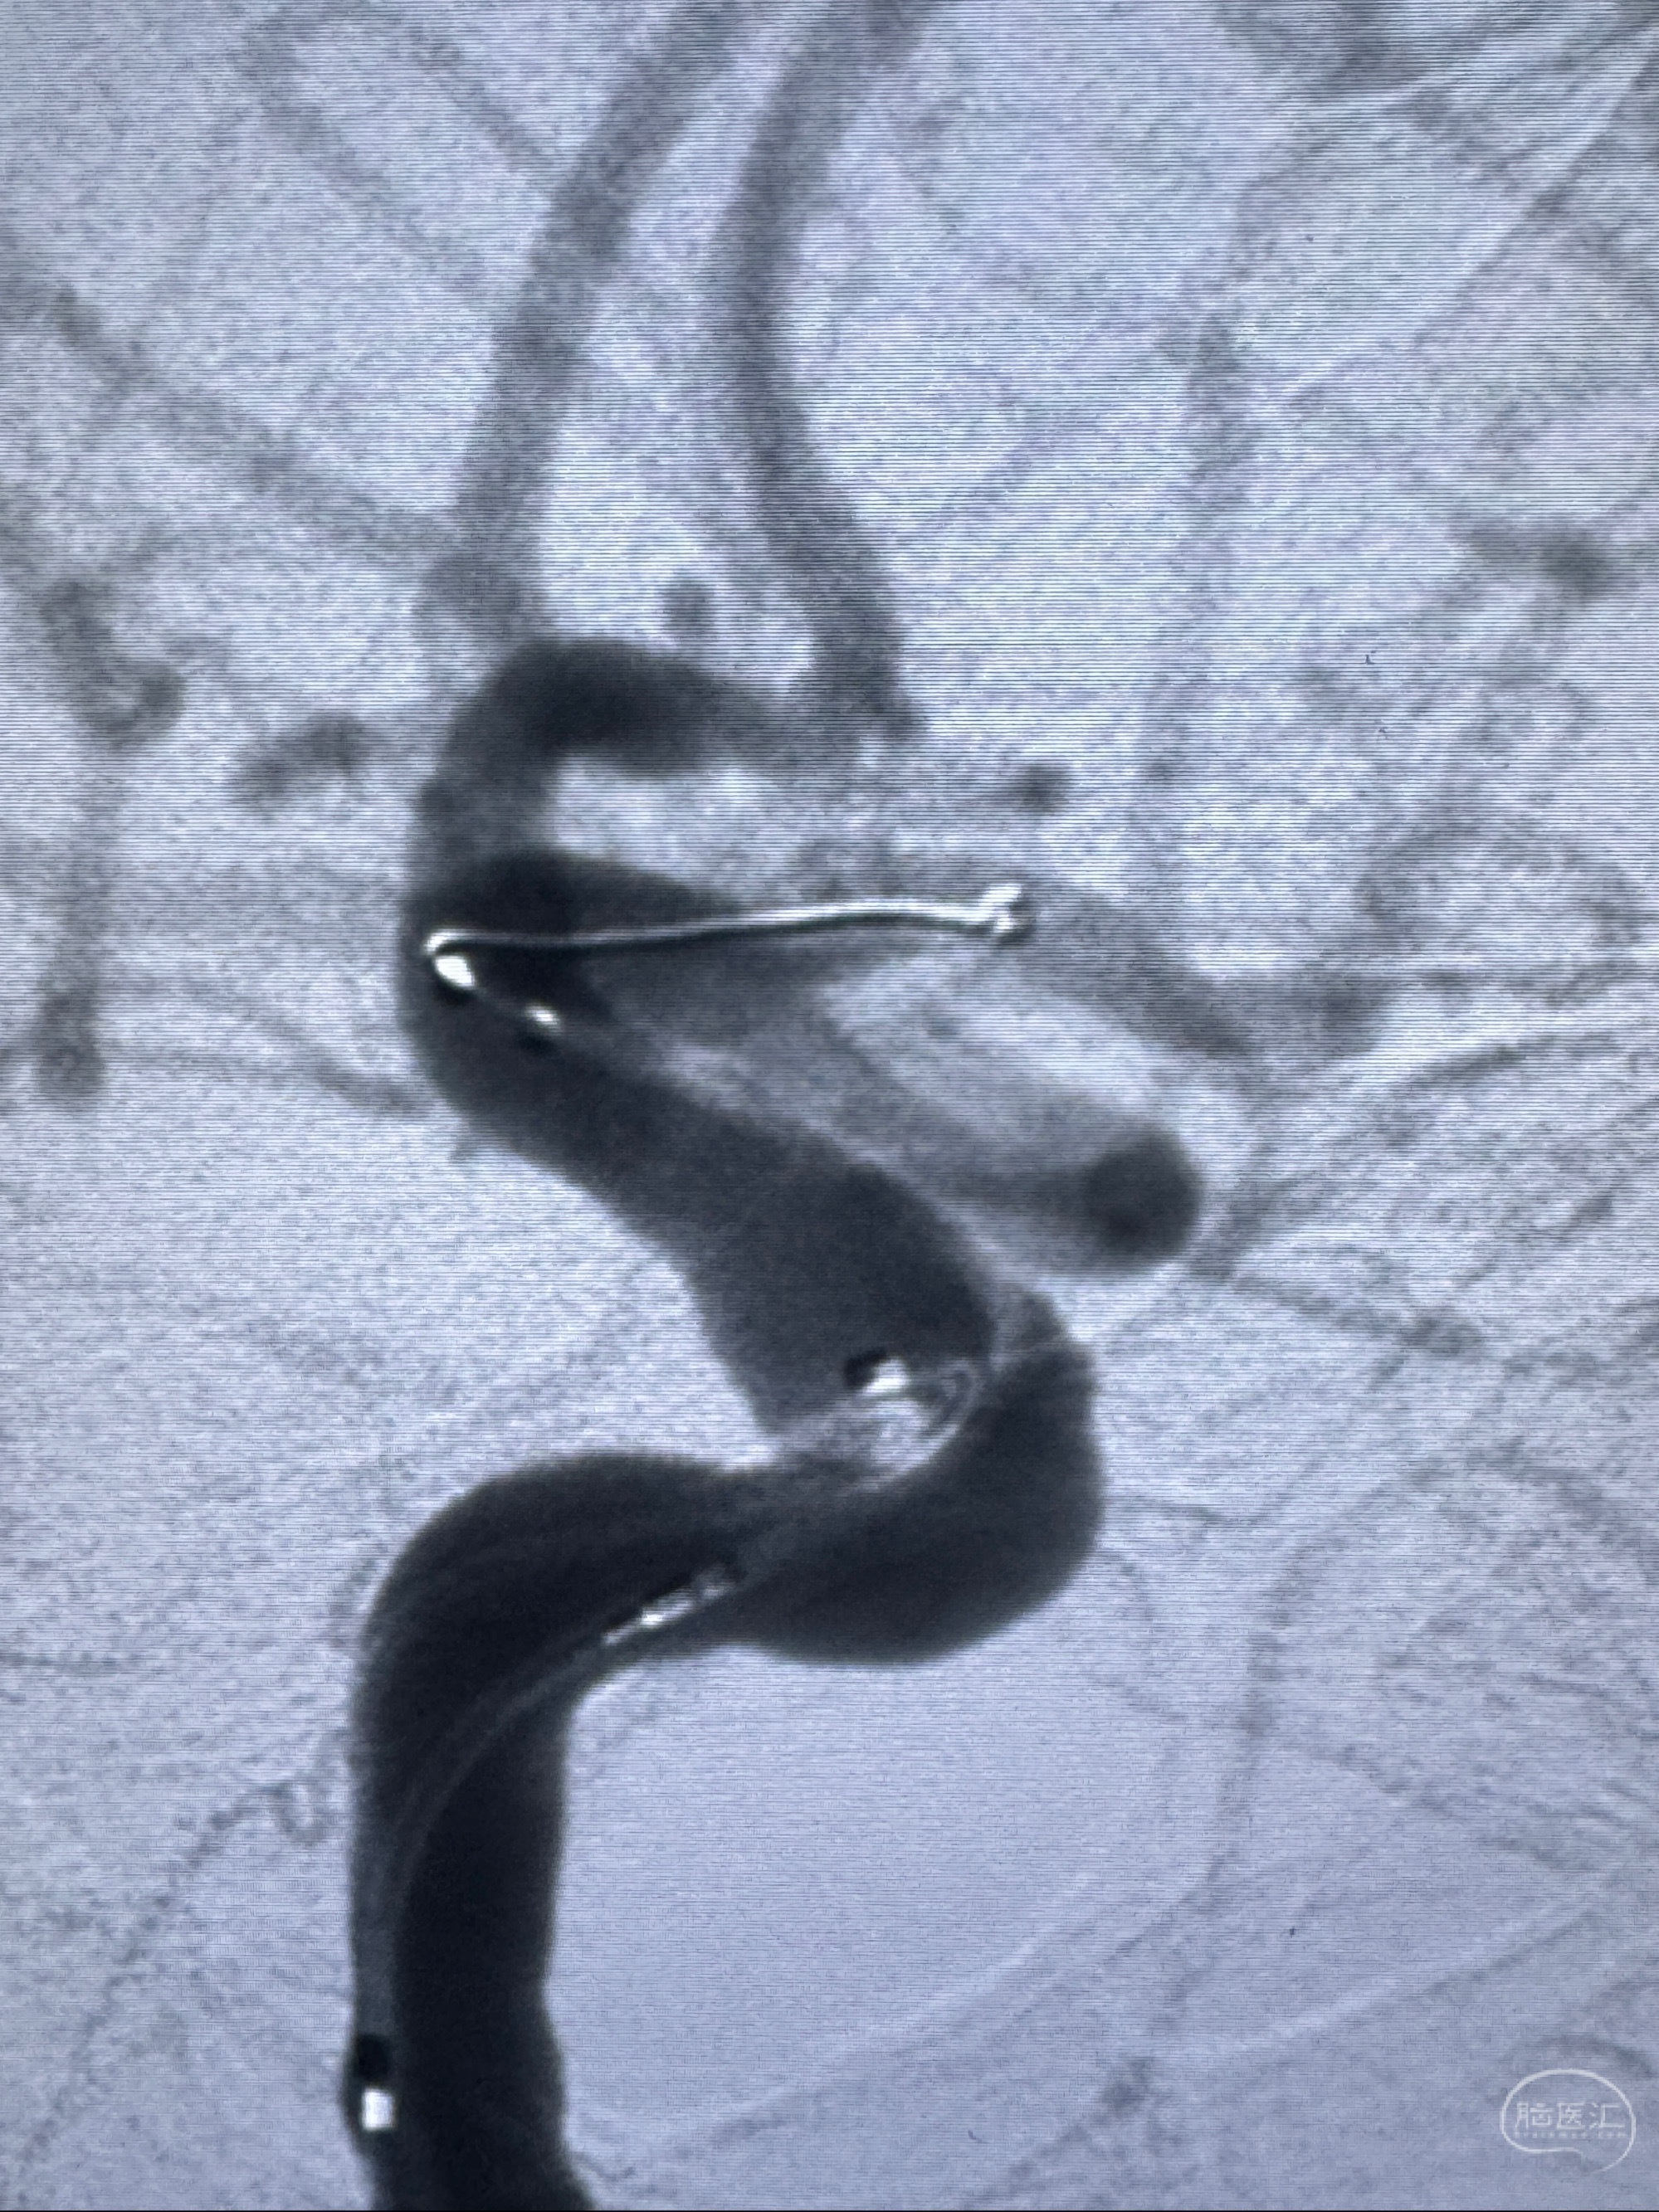

2023-11-13DSA:左侧颈内动脉眼动脉后壁动脉瘤

2023-11-29全麻下行NeuroformEZ4.5-20mm支架辅助栓塞